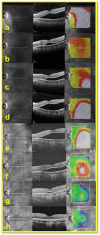

Figure 2

Serial SD-OCT Scans: a) Day of Pneumopexy (PP)– 14 Months prior to Micropulse Laser (MPL), b) Two Months after PP – 12 Months prior to MPL, c) Six Months after PP – Eight Months prior to MPL, d) 14 Months after PP - Day of MPL, e) Two Weeks after MPL, f) Two Months after MPL, g) Four Months after MPL, h) 34 Months after MPL.